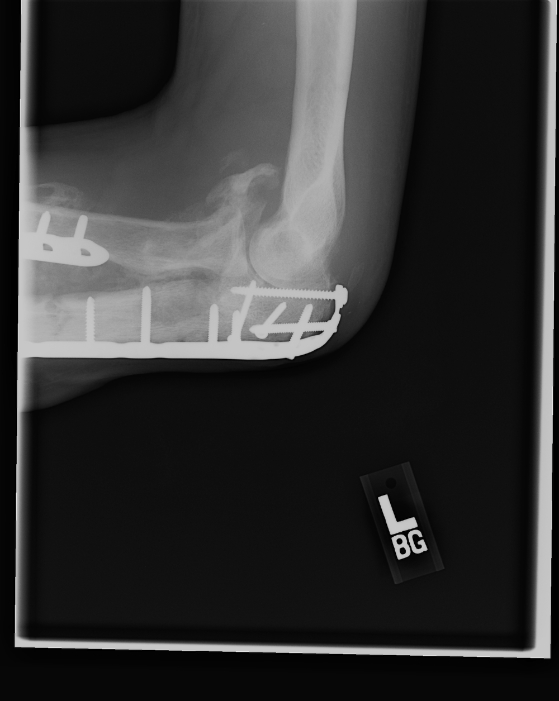

Nov 23, 2007 This picture shows both of the attachments that were used to stabilize his arm. |